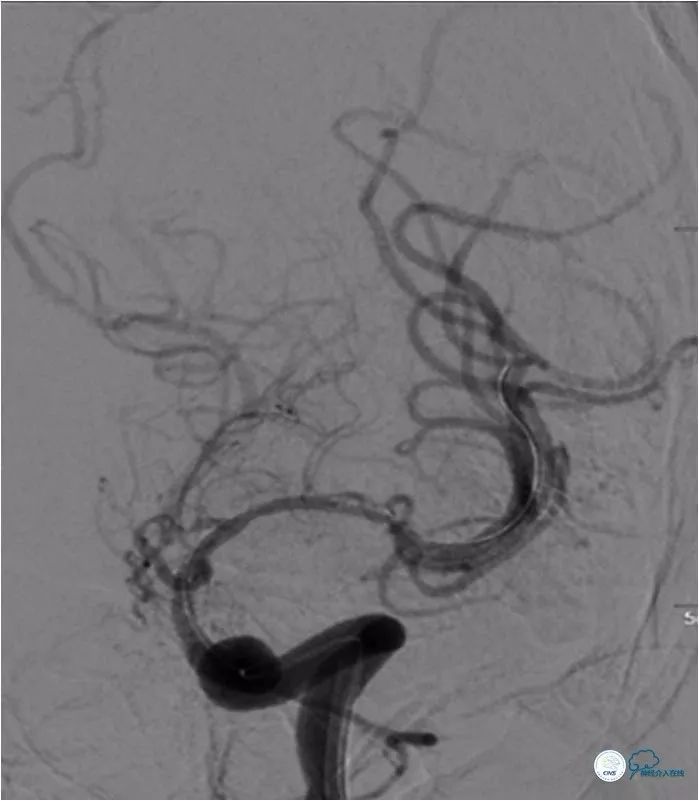

DSA(2018-4-12):左大脑中动脉支架术后再狭窄(图7)。

图7